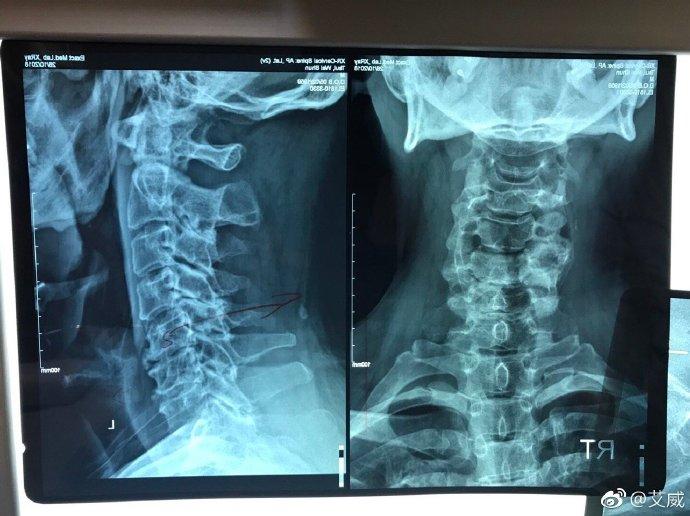

2019年3月 , 艾威的3节脊椎移了位 , 他开玩笑地称要远离低头族 , 让网友们放心 , 目前已经在治疗中了 。